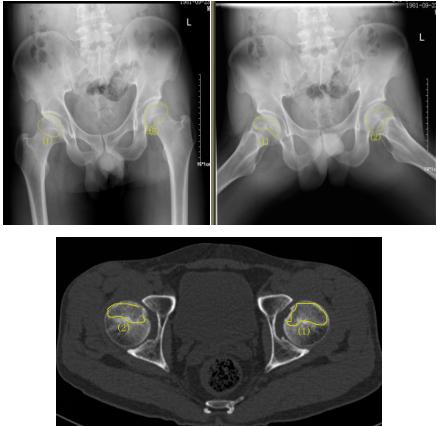

诊断:双髋疼痛,医生确诊为早期股骨头坏死

37岁的患者吴先生反复双髋疼痛2月余,听说泸州市中医院在治疗骨科疾病方面很有经验,遂来到医院治疗。经检查,吴先生双侧股骨头坏死(II期),如不及时进行手术治疗,他的股骨头将进一步坏死至骨头塌陷,引发关节炎,严重时,必须行关节置换术。这样,将会给吴先生的生活质量及经济带来严重负担。

术前报告显示患者双侧股骨头坏死